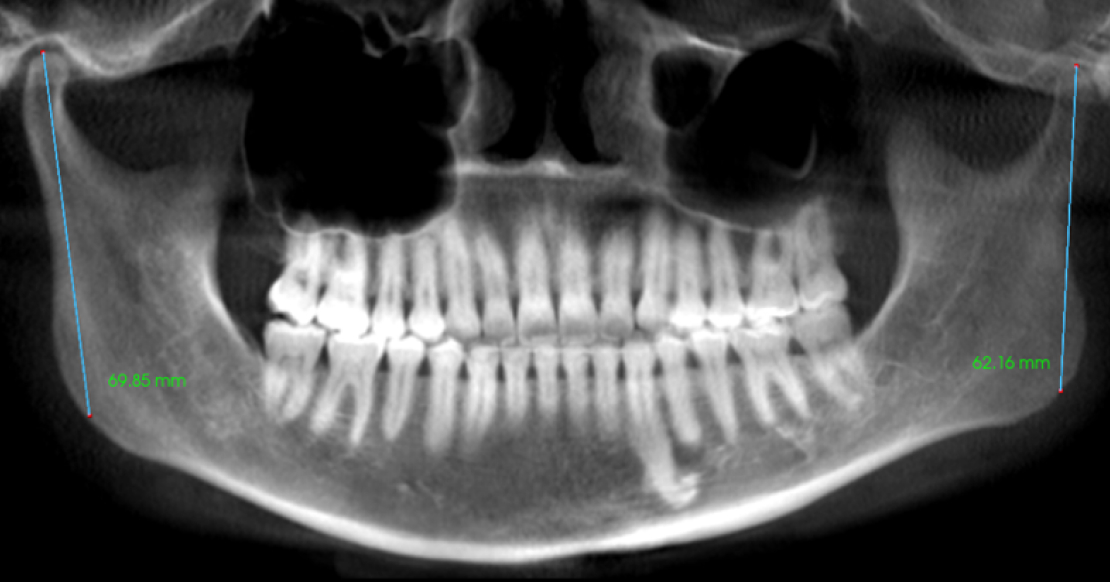

In addition to the size of the condyle, a normal shape of the condyle indicates protection for the articular disk, signifying that the articular cartilage is safeguarded. However, when there’s a disruption of the articular cartilage or the growth center, it results in a loss of vertical dimension in the mandibular condyle, leading to shorter ramus lengths.

The height from the top of the condyle to the angle of the ramus (gonion) in adult patients is 60–70 mm. For a 5-year-old patient, the expected height is 40 mm, with 2–3 mm of growth annually. An adult patient with values below these ranges suggests arrested development. In growing patients, measurements below average indicate herniation of the articular disk.”